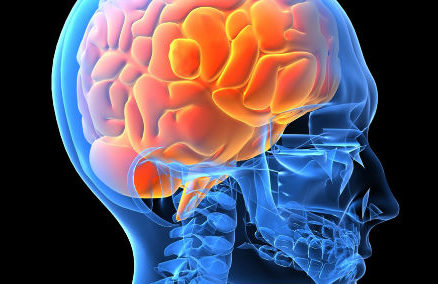

¿Por qué olvidamos lo que comimos ayer pero recordamos el primer beso durante el resto de nuestra vida? Los científicos creen que el efecto...